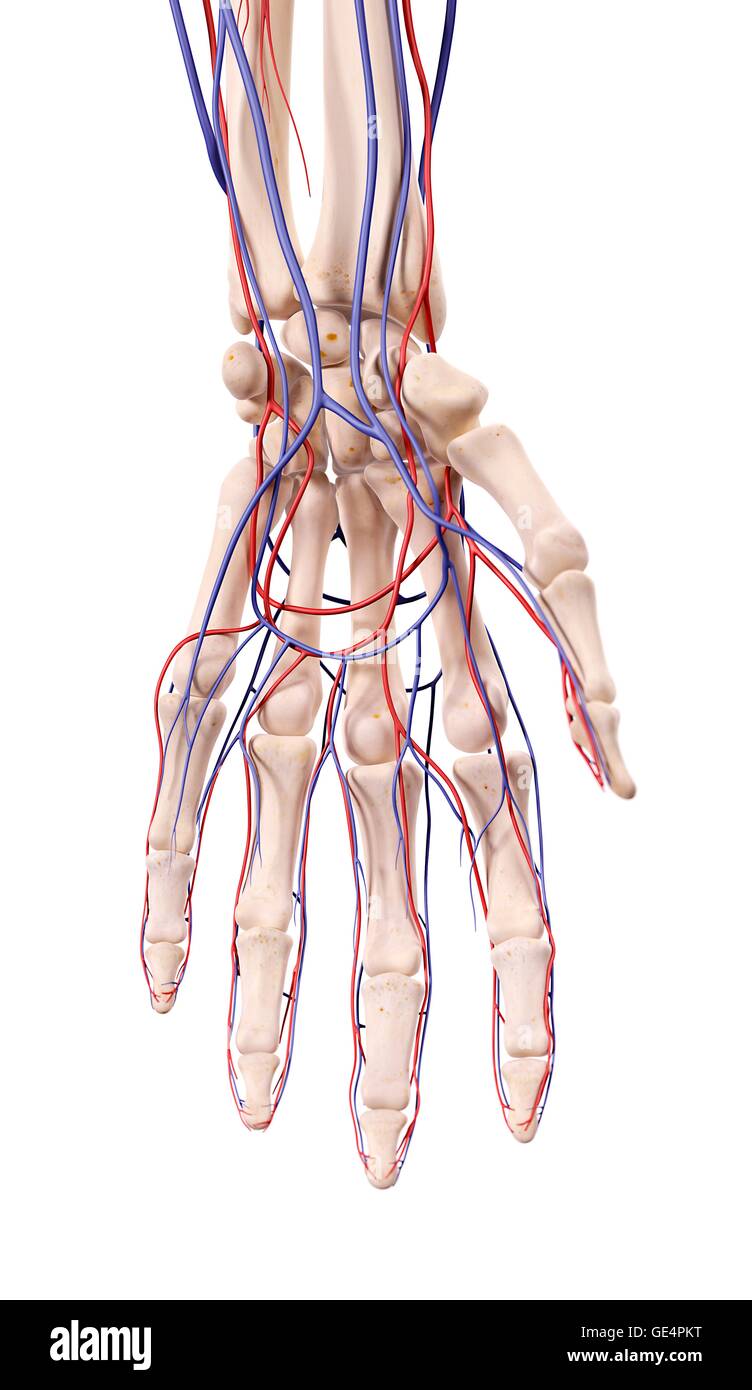

Venas de la mano. 3d fotografías e imágenes de alta resolución Alamy

Arterias y venas de la mano fotografías e imágenes de alta resolución Página 2 Alamy